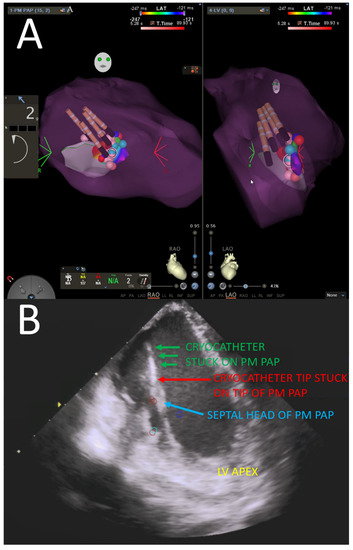

- Rivera, S.; Ricapito, M.D.L.P.; Espinoza, J.; Belardi, D.; Albina, G.; Giniger, A.; Roux, J.-F.; Ayala-Paredes, F.; Scazzuso, F. Cryoablation for ventricular arrhythmias arising from the papillary muscles of the left ventricle guided by intracardiac echocardiography and image integration. JACC Clin. Electrophysiol. 2015, 1, 509–516. [Google Scholar] [CrossRef]

- Rivera, S.; Ricapito, M.d.l.P.; Tomas, L.; Parodi, J.; Bardera Molina, G.; Banega, R.; Bueti, P.; Orosco, A.; Reinoso, M.; Caro, M.; et al. Results of cryoenergy and radiofrequency-based catheter ablation for treating ventricular arrhythmias arising from the papillary muscles of the left ventricle, guided by intracardiac echocardiography and image integration. Circ. Arrhythm. Electrophysiol. 2016, 9, e003874. [Google Scholar] [CrossRef] [PubMed] [Green Version]

- Gordon, J.P.; Liang, J.J.; Pathak, R.K.; Zado, E.S.; Garcia, F.C.; Hutchinson, M.D.; Santangeli, P.; Schaller, R.D.; Frankel, D.S.; Marchlinski, F.E.; et al. Percutaneous cryoablation for papillary muscle ventricular arrhythmias after failed radiofrequency catheter ablation. J. Cardiovasc. Electrophysiol. 2018, 29, 1654–1663. [Google Scholar] [CrossRef]